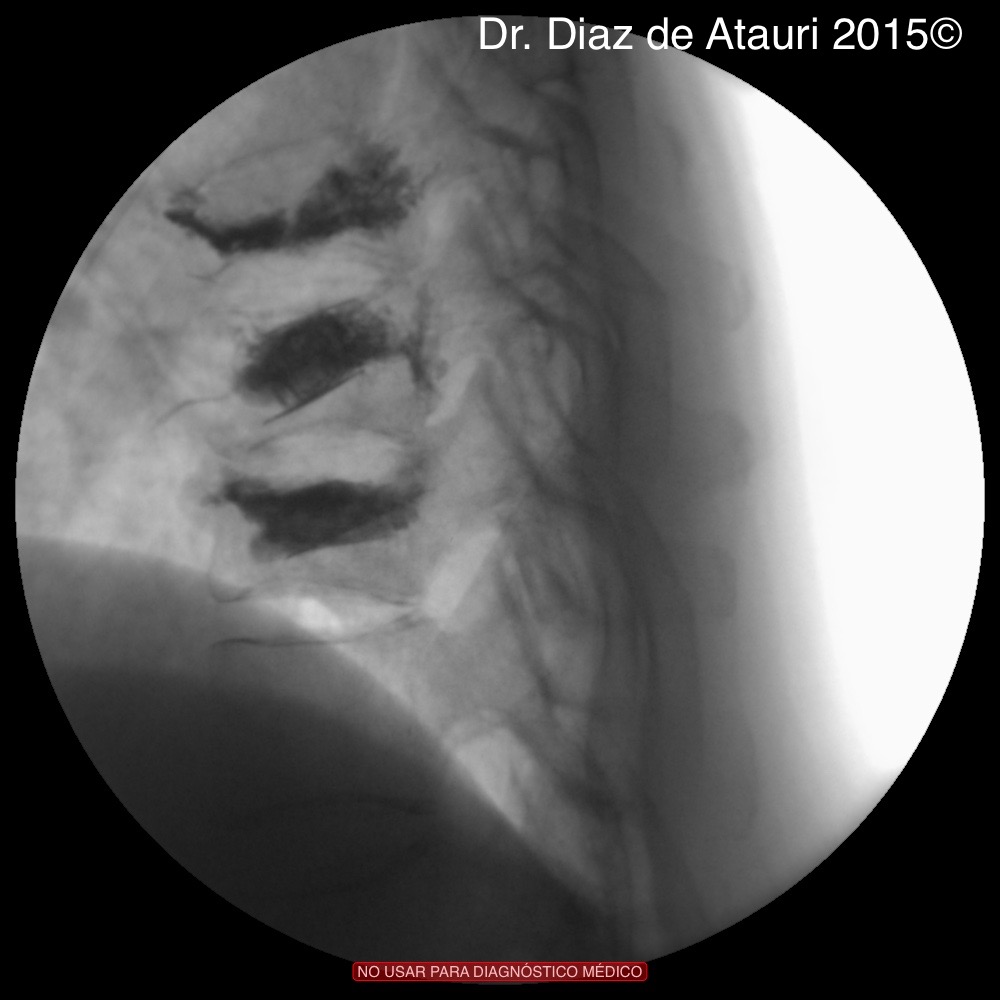

Puedes ver imágenes de una fractura y de la técnica quirúrgica de un caso real del 2015 tras este texto.